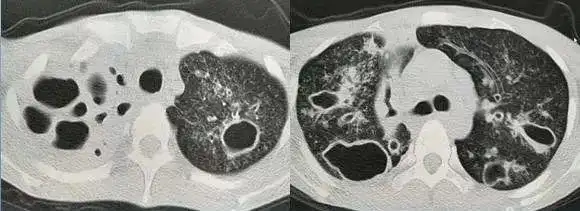

从ct上判断肺结核传染性的三种征象

多发小结节状卫星灶的肺结核

陈起航教授肺结核的影像学评价遏制终止终结肺结核2